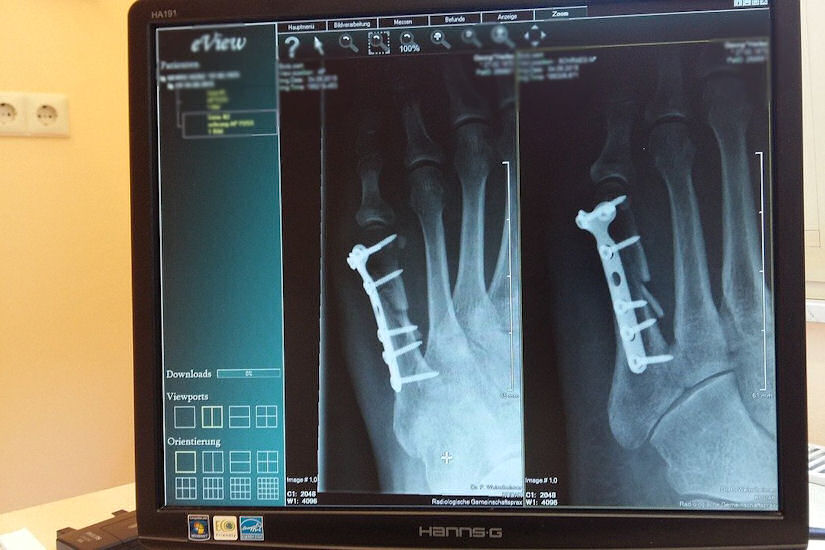

Najčešći su slučajevi prijeloma zapešća, ali bilo je i onih koji su prošli s kompleksnijim prijelomima koji su zahtjevali operativni zahvat. Jedna naša čitateljica prenijela nam je iskustvo u obitelji, a koje završilo i dvostrukim prijelomom.